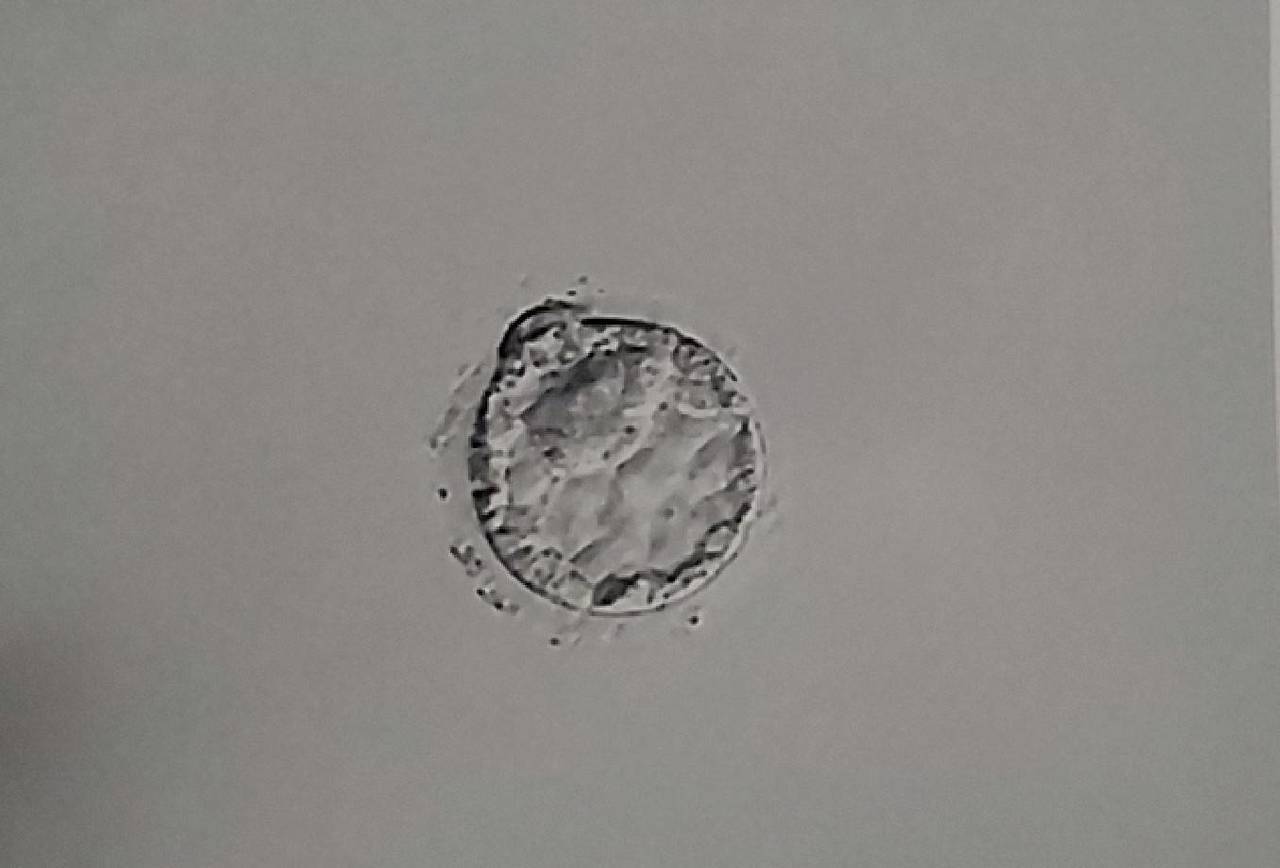

「卵子の質」とは何か

「卵子の質が良い」とは具体的にどういう状態を指すのでしょうか。

卵子の質を示す要素

内容・妊活への影響

染色体の正常性

最も重要。染色体異常のない卵子は受精・着床・妊娠継続の可能性が高い。加齢とともに染色体異常率が上昇

ミトコンドリアの機能

卵子の「エネルギー工場」。ミトコンドリア機能が高いほど受精・胚発育がスムーズ。酸化ストレスで低下

紡錘体の機能

受精時の染色体分離に関わる。紡錘体の異常が染色体異常の原因になる

卵子の成熟度

MII期(第二減数分裂中期)まで成熟した卵子が受精能を持つ。未成熟卵は受精率が低い

卵子の透明帯の状態

精子が侵入するための膜。硬化すると受精率が低下

これらの要素はすべて相互に関連しており、特に「ミトコンドリア機能」と「染色体の正常性」は年齢・酸化ストレス・体の環境によって大きく左右されます。